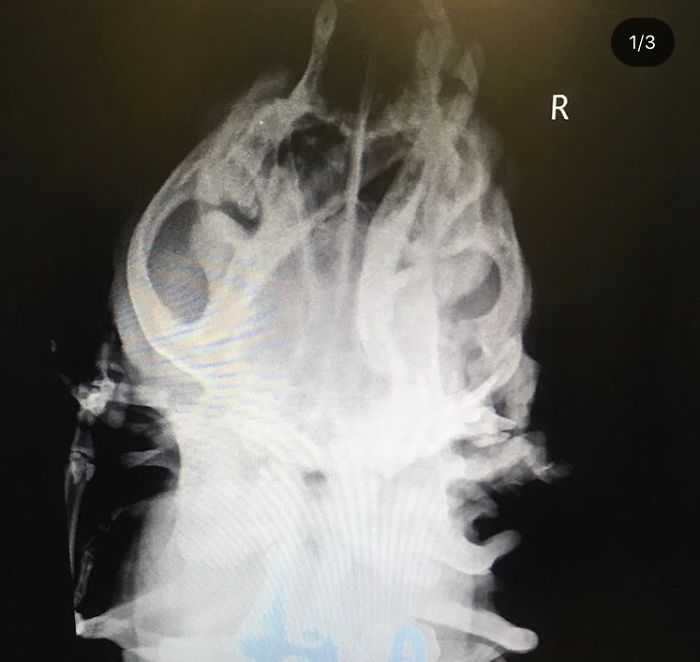

As you can see in the picture below, Toad has 2 ears like any other dog but when you lift the right ear, get ready for a shock, there is another mouth there. This mouth even has teeth and saliva glands as well. Although most people find these dogs disgusting, the misfit rescue staff finds them lovely.

The 2nd mouth does not have any jaw so it cannot chew anything. It still produces saliva and is also connected with the original mouth. The extra mouth has three teeth which are cleaned by a vet often.

Despite her deformity, Toad is a healthy and sweet dog. Her X-rays also do not show any serious condition. The theory is that in the womb she might have absorbed one of her twins.